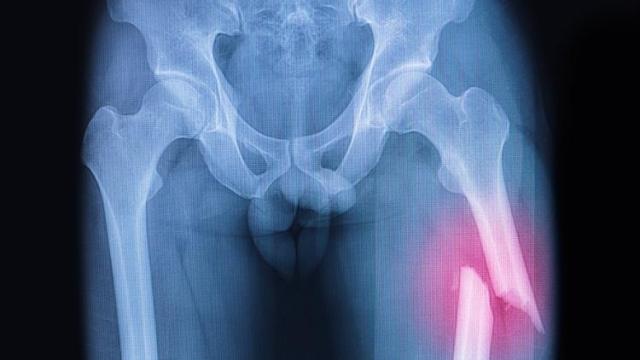

Reumatología